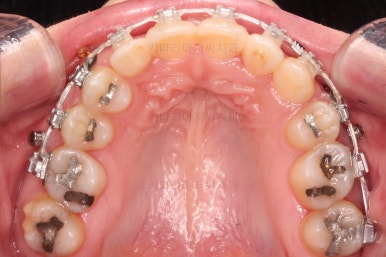

치료 종료 시 입안의 모습입니다.

윗니만 발치를 했지만 교합이 잘 맞고요.

한 쪽 송곳니가 없지만 기능적으로 전혀 문제를 못느끼실 교합을 맞춰놨고요.

위아랫니 가지런해졌고요.

대신 중앙선은 약간 틀어져 있는데요.

한 쪽은 송곳니가 없고 한 쪽은 작은 어금니를 발치했기 때문인데요.

18개월이라는 짧은 기간동안 부정교합, 덧니, 심지어 매복치아까지 개선했는데 양측 치아 사이즈 문제로 생기는 중앙선 정도는 아무 문제가 안되는거죠.